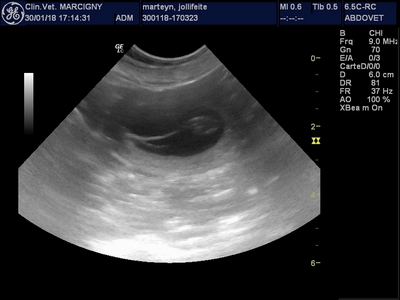

Des bébés en vue dans le bedon de Jolliffeite !!!!!

Rendez vous sur la page "mariages" pour en savoir plus !